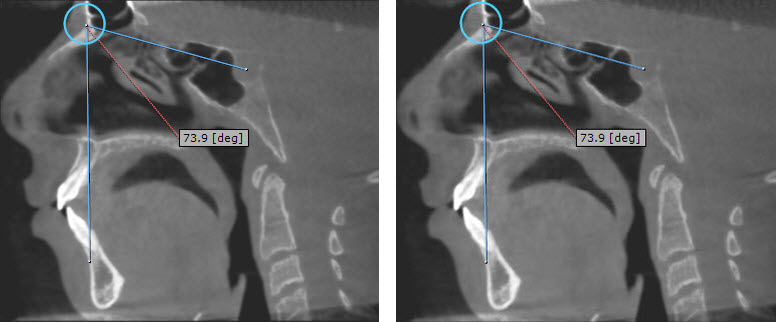

Radiographic assessment was performed using iCAT FLX V17-Series CBCT machine (Imaging Science International, ISI, PA, USA) using quick scan imaging protocol of 16cm x 13cm Field Of View (FOV) (120KV, 5mA, 4sec) and 0.3mm voxel size. Raw DICOM data were transferred to OnDemand3DApp and Invivo5 software. Linear measurements included narrowest cross-sectional area calculated in mm2, Anteroposterior (AP) and Lateral (L) dimensions of the airway at the narrowest cross-sectional area were calculated in mm as shown in Fig. (1).

Results: High significance difference could be seen in some angular, linear and volumetric measurements between the two groups suggesting high accuracy of CBCT measurements.